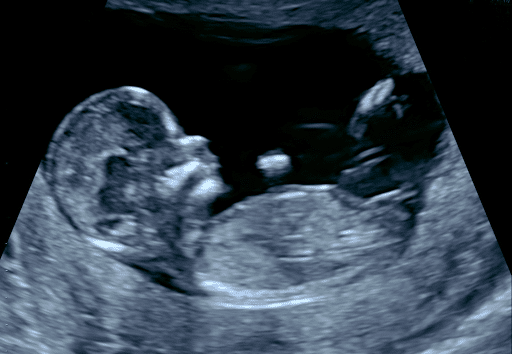

Échographie bienveillante pour des moments précieux de maternité et santé féminine.

Le Cabinet d’échographie obstétricale et gynécologique Sud Loire, situé à Saint-Sébastien-sur-Loire, propose des services d’échographie pour les femmes enceintes et les consultations gynécologiques. Les patientes peuvent bénéficier d’évaluations précises de leur santé reproductive et du suivi de la grossesse, garantissant un accompagnement adéquat tout au long de ces étapes essentielles. Consultations sur rendez-vous.